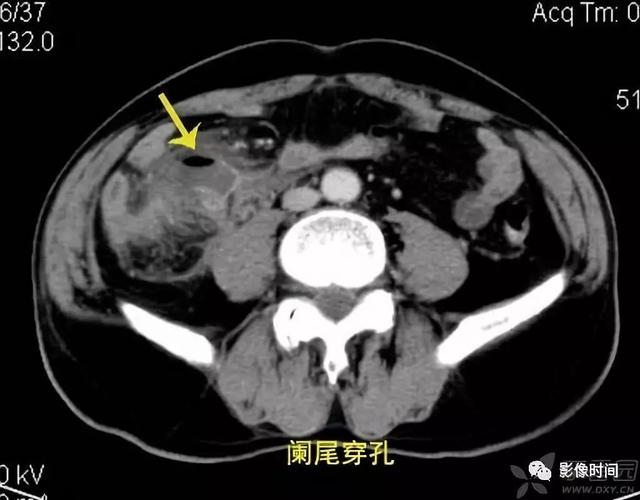

ct片上总是找不到阑尾3步法教你快速定位

急性阑尾炎的ct表现

急性阑尾炎ct诊断

全面讲解正常阑尾和阑尾炎的ct表现